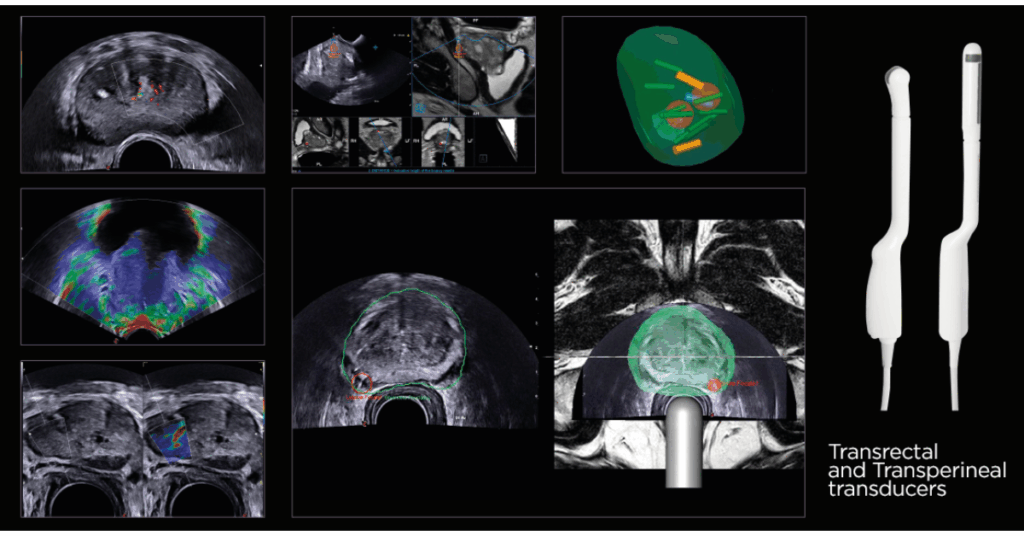

Komplexní řešení umožňuje detekci, sledování a léčbu širokého spektra onemocnění – od hepatologie a urologie, přes radiologii, gastroenterologii, gynekologii až po sportovní medicínu. Technologie, jako fúzní zobrazování (US-MRI), Virtual Navigator nebo UroFusion, podporované umělou inteligencí, poskytují přesné vedení intervencí a cílených biopsií v reálném čase.

Díky funkcím jako BreastNav™MRI, QPack, QElaXto 2D či Single Crystal sondám nabízí MyLab™X9 dokonalé zobrazení měkkých tkání, vaskularizace i strukturálních detailů s frekvencí až 25 MHz.